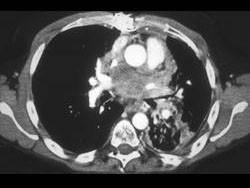

问题 男,45岁,咳嗽,咯血2月余,有20余年吸烟史,请结合影像学检查图,选出最可能的诊断 ( )

选项 A、肺囊肿 B、肺错构瘤 C、小细胞肺癌 D、肺脓肿 E、肺结核

答案 C